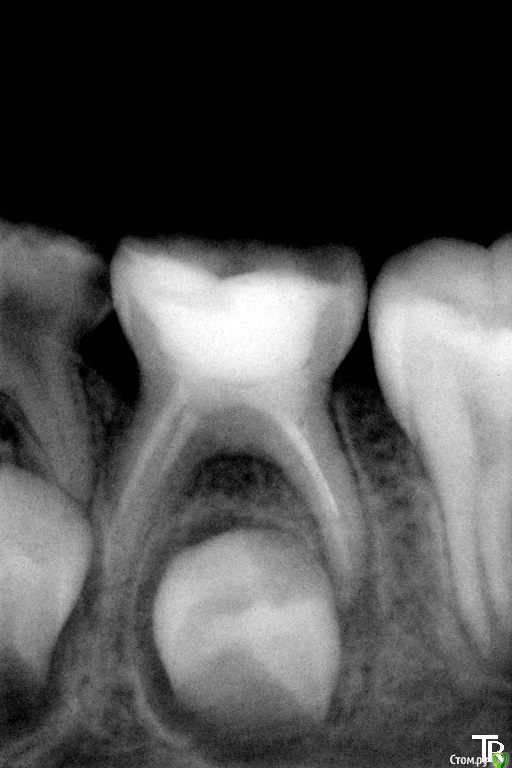

crown Опубликовано 5 июля, 2016 Поделиться Опубликовано 5 июля, 2016 7 лет, зуб 6.3 не беспокоит, разрушена вестибулярная стенка. Как определить это воспалительная резорбция или физиологическая? Если физиологическая, то есть ли смысл пломбировать канал или нет? Приостановится она или нет? И на сколько хватит такого лечения? Чем потом восстановить зуб? Нью смайл кто нить пользуется? Ссылка на комментарий

Джима Опубликовано 5 июля, 2016 Поделиться Опубликовано 5 июля, 2016 (изменено) 7 лет, зуб 6.3 не беспокоит, разрушена вестибулярная стенка. Как определить это воспалительная резорбция или физиологическая? Если физиологическая, то есть ли смысл пломбировать канал или нет? Приостановится она или нет? И на сколько хватит такого лечения? Чем потом восстановить зуб? Нью смайл кто нить пользуется?резорбция чего, апекса? физиологическая, только-только началась. если десна бессимптомная, то точно физиологическая. пломбировать смысл есть, никогда не знаешь, достоит оно до смены, или разболится из-за чего-то. детки хилые пошли, осень, орви, бронхит, АБ - привет, периостит. плавали, знаем. приостановится ли - да неважно, в общем. думаю, года два зуб точно простоит ещё, на третий качаться начнёт. Восстанавливаю пломбой, Нью смайл на форуме Доктор Саша, вроде, работает, только заходит редко. Оксана, кажется, тоже хотела. Если смущает просто пломба - сделайте непрямую. Изменено 5 июля, 2016 пользователем Джима Ссылка на комментарий